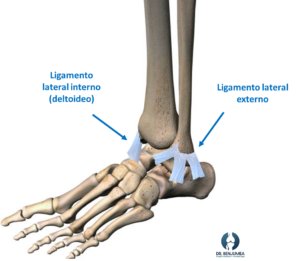

El tobillo está sostenido por varios ligamentos. En la parte externa, hay tres ligamentos que forman un triángulo, siendo el ligamento peroneoastragalino anterior (que une principalmente a dos huesos, el astrágalo con el peroné), el afectado con más frecuencia dado que es el más débil. En la parte interna trabaja el ligamento deltoideo de un grosor considerable, por lo que su lesión aislada es menos frecuente.

El tobillo se encuentra sujetado fundamentalmente por estos ligamentos, y cuando existe una lesión de alguno de ellos, además del dolor y la incapacidad para andar, puede desarrollarse una inestabilidad a largo plazo. La inestabilidad, al igual que el esguince de tobillo, es más frecuente en el lado externo.